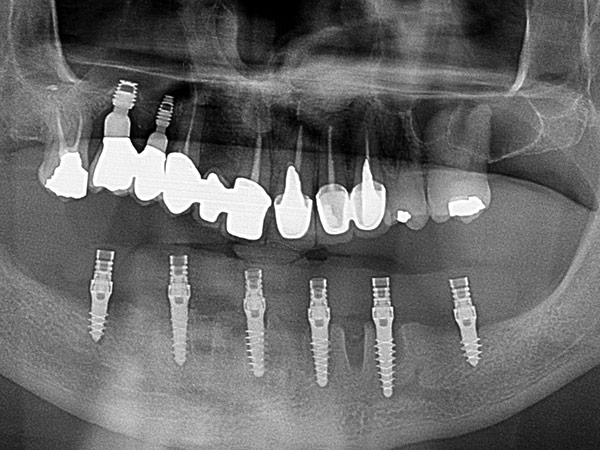

Impianti AZ Implant DX in riabilitazione completa inferiore fissa avvitata con grave terza classe scheletrica

Impianti dentali in riabilitazione inferiore per supportare struttura fissa avvitata con grave terza classe scheletrica.

L’intervento nello specifico è stato realizzato dal Dr. Andrea Tomasinelli con componenti protesiche progettate e fornite da AZ Implant.